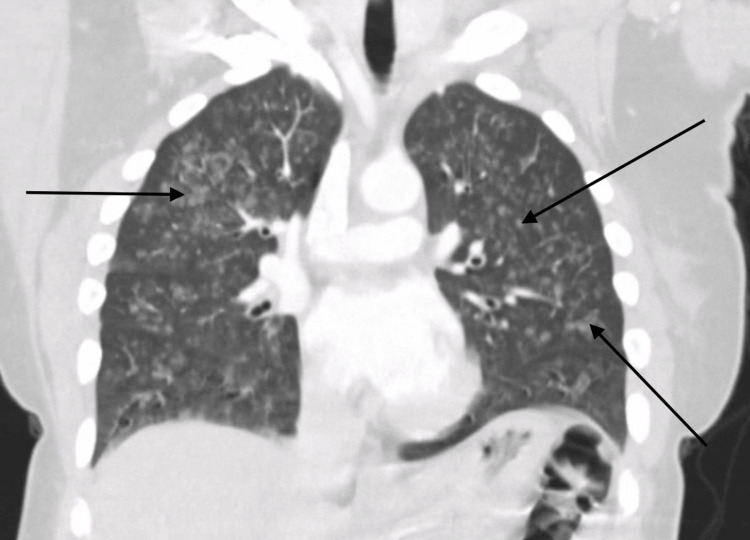

On initial evaluation, the patient was alert and oriented but noted to be hypoxic with oxygen saturation of 91% on room air and required supplemental oxygen. Chest X-ray initially revealed bilateral patchy opacities (Figure 1), and contrast-enhanced computed tomography (CT) of the chest revealed diffuse ground-glass opacities (GGOs) (Figure 2). Laboratory tests showed an initial hemoglobin level of 13.3 g/dL, which precipitously dropped to 9.3 g/dL (reference range: 12.0-16.0 g/dL) within 24 hours. Urine toxicology was positive for cannabis, while renal function and coagulation studies were unremarkable.

Typical pulmonary radiological findings of DAH include diffuse bilateral alveolar infiltrates, which are often described as GGOs on chest CT scans or consolidations on chest X-rays. However, in the early stages, chest X-rays can fail to capture the full extent of the disease, and serial X-rays or chest CT should be considered for a prompt and accurate diagnosis. The infiltrates observed in DAH are typically patchy or confluent and can progress rapidly, reflecting the alveolar spaces filling with blood. This pattern is usually non-segmental and predominantly affects the dependent lung regions [ref. 10].

Chest CT is more sensitive than chest X-rays in detecting the features of DAH. GGOs, as seen on CT scans, are more prominent and provide a clearer delineation of the extent of alveolar hemorrhage compared to consolidations. Unlike infectious pneumonia, the infiltrates in DAH generally lack air bronchograms, which can aid in distinguishing between these conditions. In the acute setting, chest imaging may appear normal in up to 50% of cases, which highlights that normal radiological findings do not rule out the diagnosis. Rapid imaging assessment combined with clinical evaluation is crucial for timely identification and intervention in cases of DAH [ref. 11].